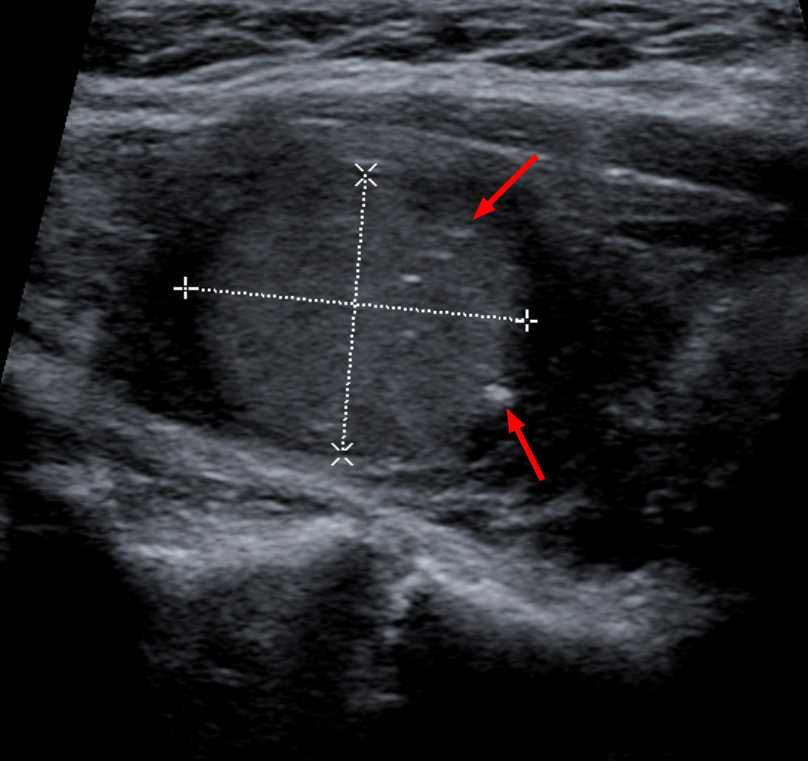

갑상선 병변의 세침 흡인 검사를 통해 다른 유형의 갑상선 병변과 구별하여 진단한다.[15] 현미경 검사에서는 부갑상선 세포의 과형성 및 아밀로이드 기질이 나타난다.